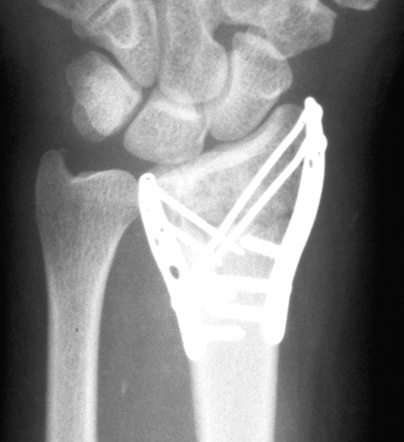

Case 2 Postop